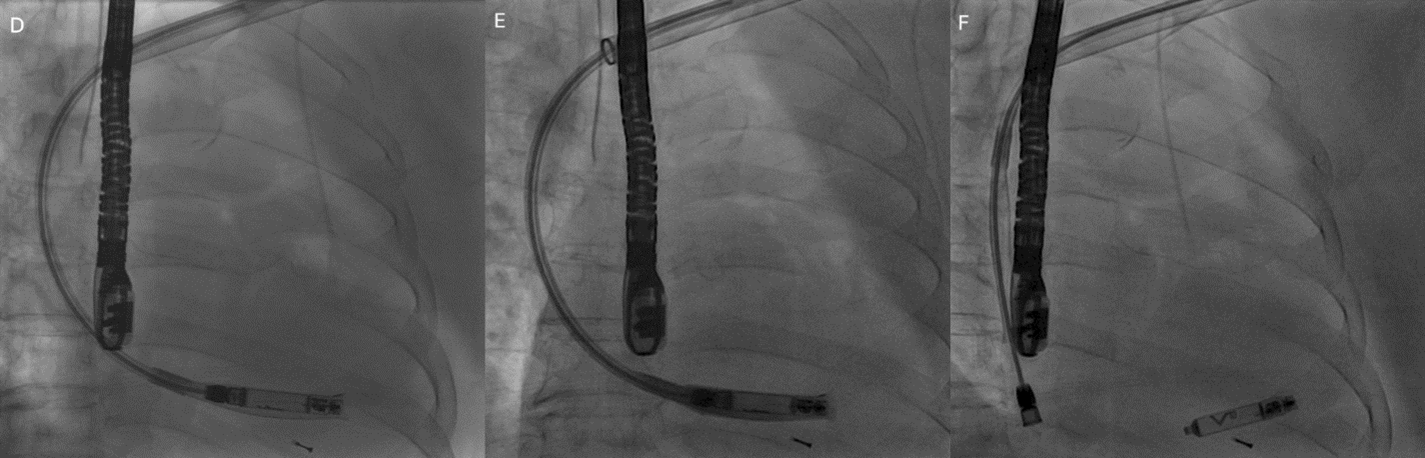

Given her recurrent pocket and lead issues, low ventricular pacing requirement, and chronic oral anticoagulation, a leadless pacemaker was selected. During the same session, an AVEIR VR Leadless Pacemaker (Abbott) was implanted via the left subclavian vein rather than the conventional femoral route. Subclavian access was selected to avoid creating new femoral access and to accommodate the patient’s request for quicker recovery, as her chronic back pain limited tolerance for prolonged bed rest.

The AVEIR delivery sheath was advanced only to the distal subclavian vein to avoid vascular injury. The steerable delivery catheter was then advanced through the sheath with the protective sleeve in place and directed across the tricuspid valve into the right ventricle (Figure D and E). The device was actively fixed along the septum, and biplane fluoroscopy with contrast injection confirmed stable positioning and adequate myocardial engagement (Figure F; Videos 1-3). Electrical testing demonstrated satisfactory pacing thresholds, sensing, and impedance.